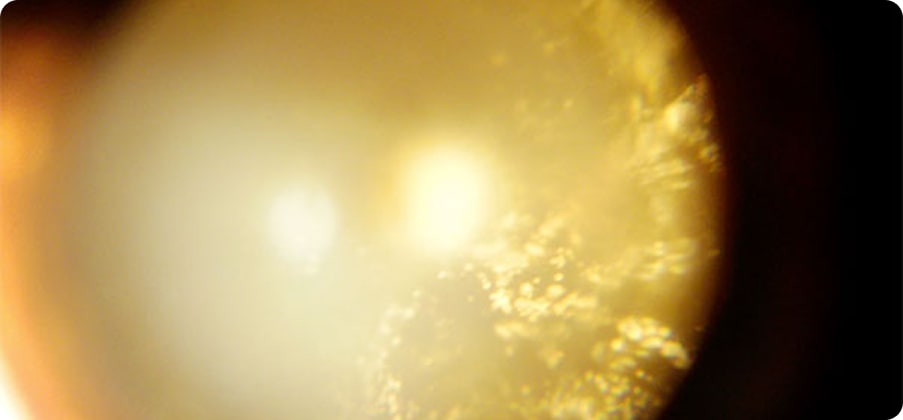

目の中にある「水晶体(すいしょうたい)」が白く濁ってしまう病気です。

水晶体は、カメラでいうレンズのような働きをしており、本来は透明で光を通して物を見るために重要な部分です。

時間経過と共に白内障は進行していき、やがては緑内障やぶどう膜炎など他の眼疾患を引き起こす原因になります。

そのため早期の治療が望まれる病気です。

大型犬では6歳くらい、小型犬では10歳くらいが発症しやすいですが、若齢の子でも発症することもあります。

さまざまな原因が存在します。代表的なものとして、遺伝によるもの、代謝によるもの、ほかの疾患から続発して起こるものがあげられます。

白内障は水晶体の混濁の程度で4つのステージに分類されます。

成熟白内障

過熟白内障

混濁は15%以下で目は見えている状態。

混濁は15%以上で目は見えている~見えづらい状態。

全体的に混濁し、目が見えない状態。

水晶体の中身が漏れ出ることで、混濁は薄くなり目は見えづらい〜少し回復し見えている状態。